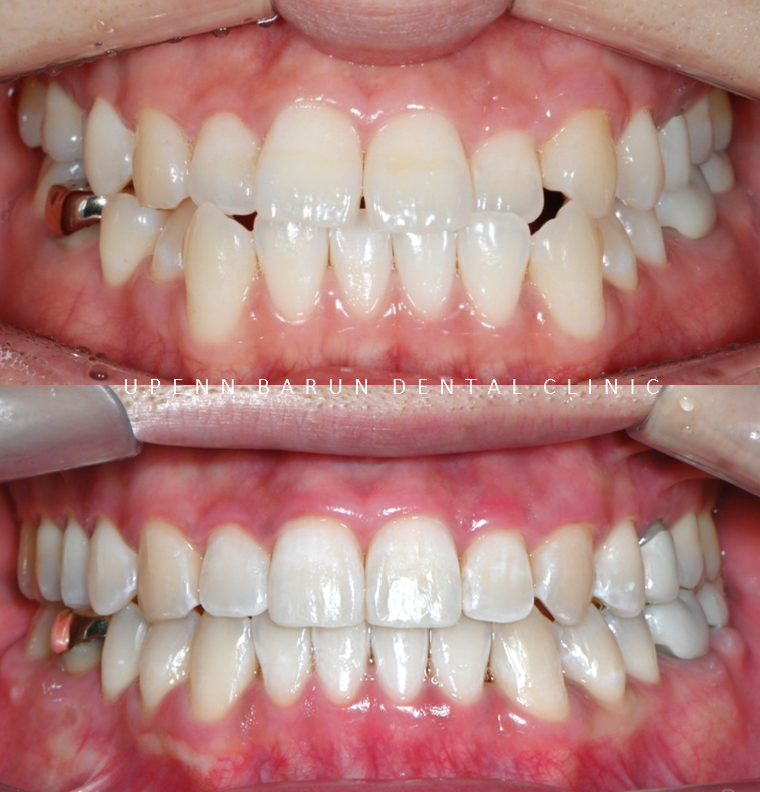

전체적으로 위,아랫니들이

제 위치를 찾으며 정리가 되었습니다!!

어금니들의 대이동이 끝이나고

클린체크의 예상대로 교정 마무리가 잘 되었어요!!

윗니와 아랫니 사이의 틈이 사라지고,

윗니를 덮고 있던 아랫니들이 제 위치를 찾으며 부정교합이 개선되었을 뿐만 아니라

정중앙선이 일치하도록 마무리 해드렸습니다 :)

교정완료 후엔

미백맛집이기도 한 유펜바른치과의 전문가미백치료로 치아들이 한층 더 밝아진 모습입니다.